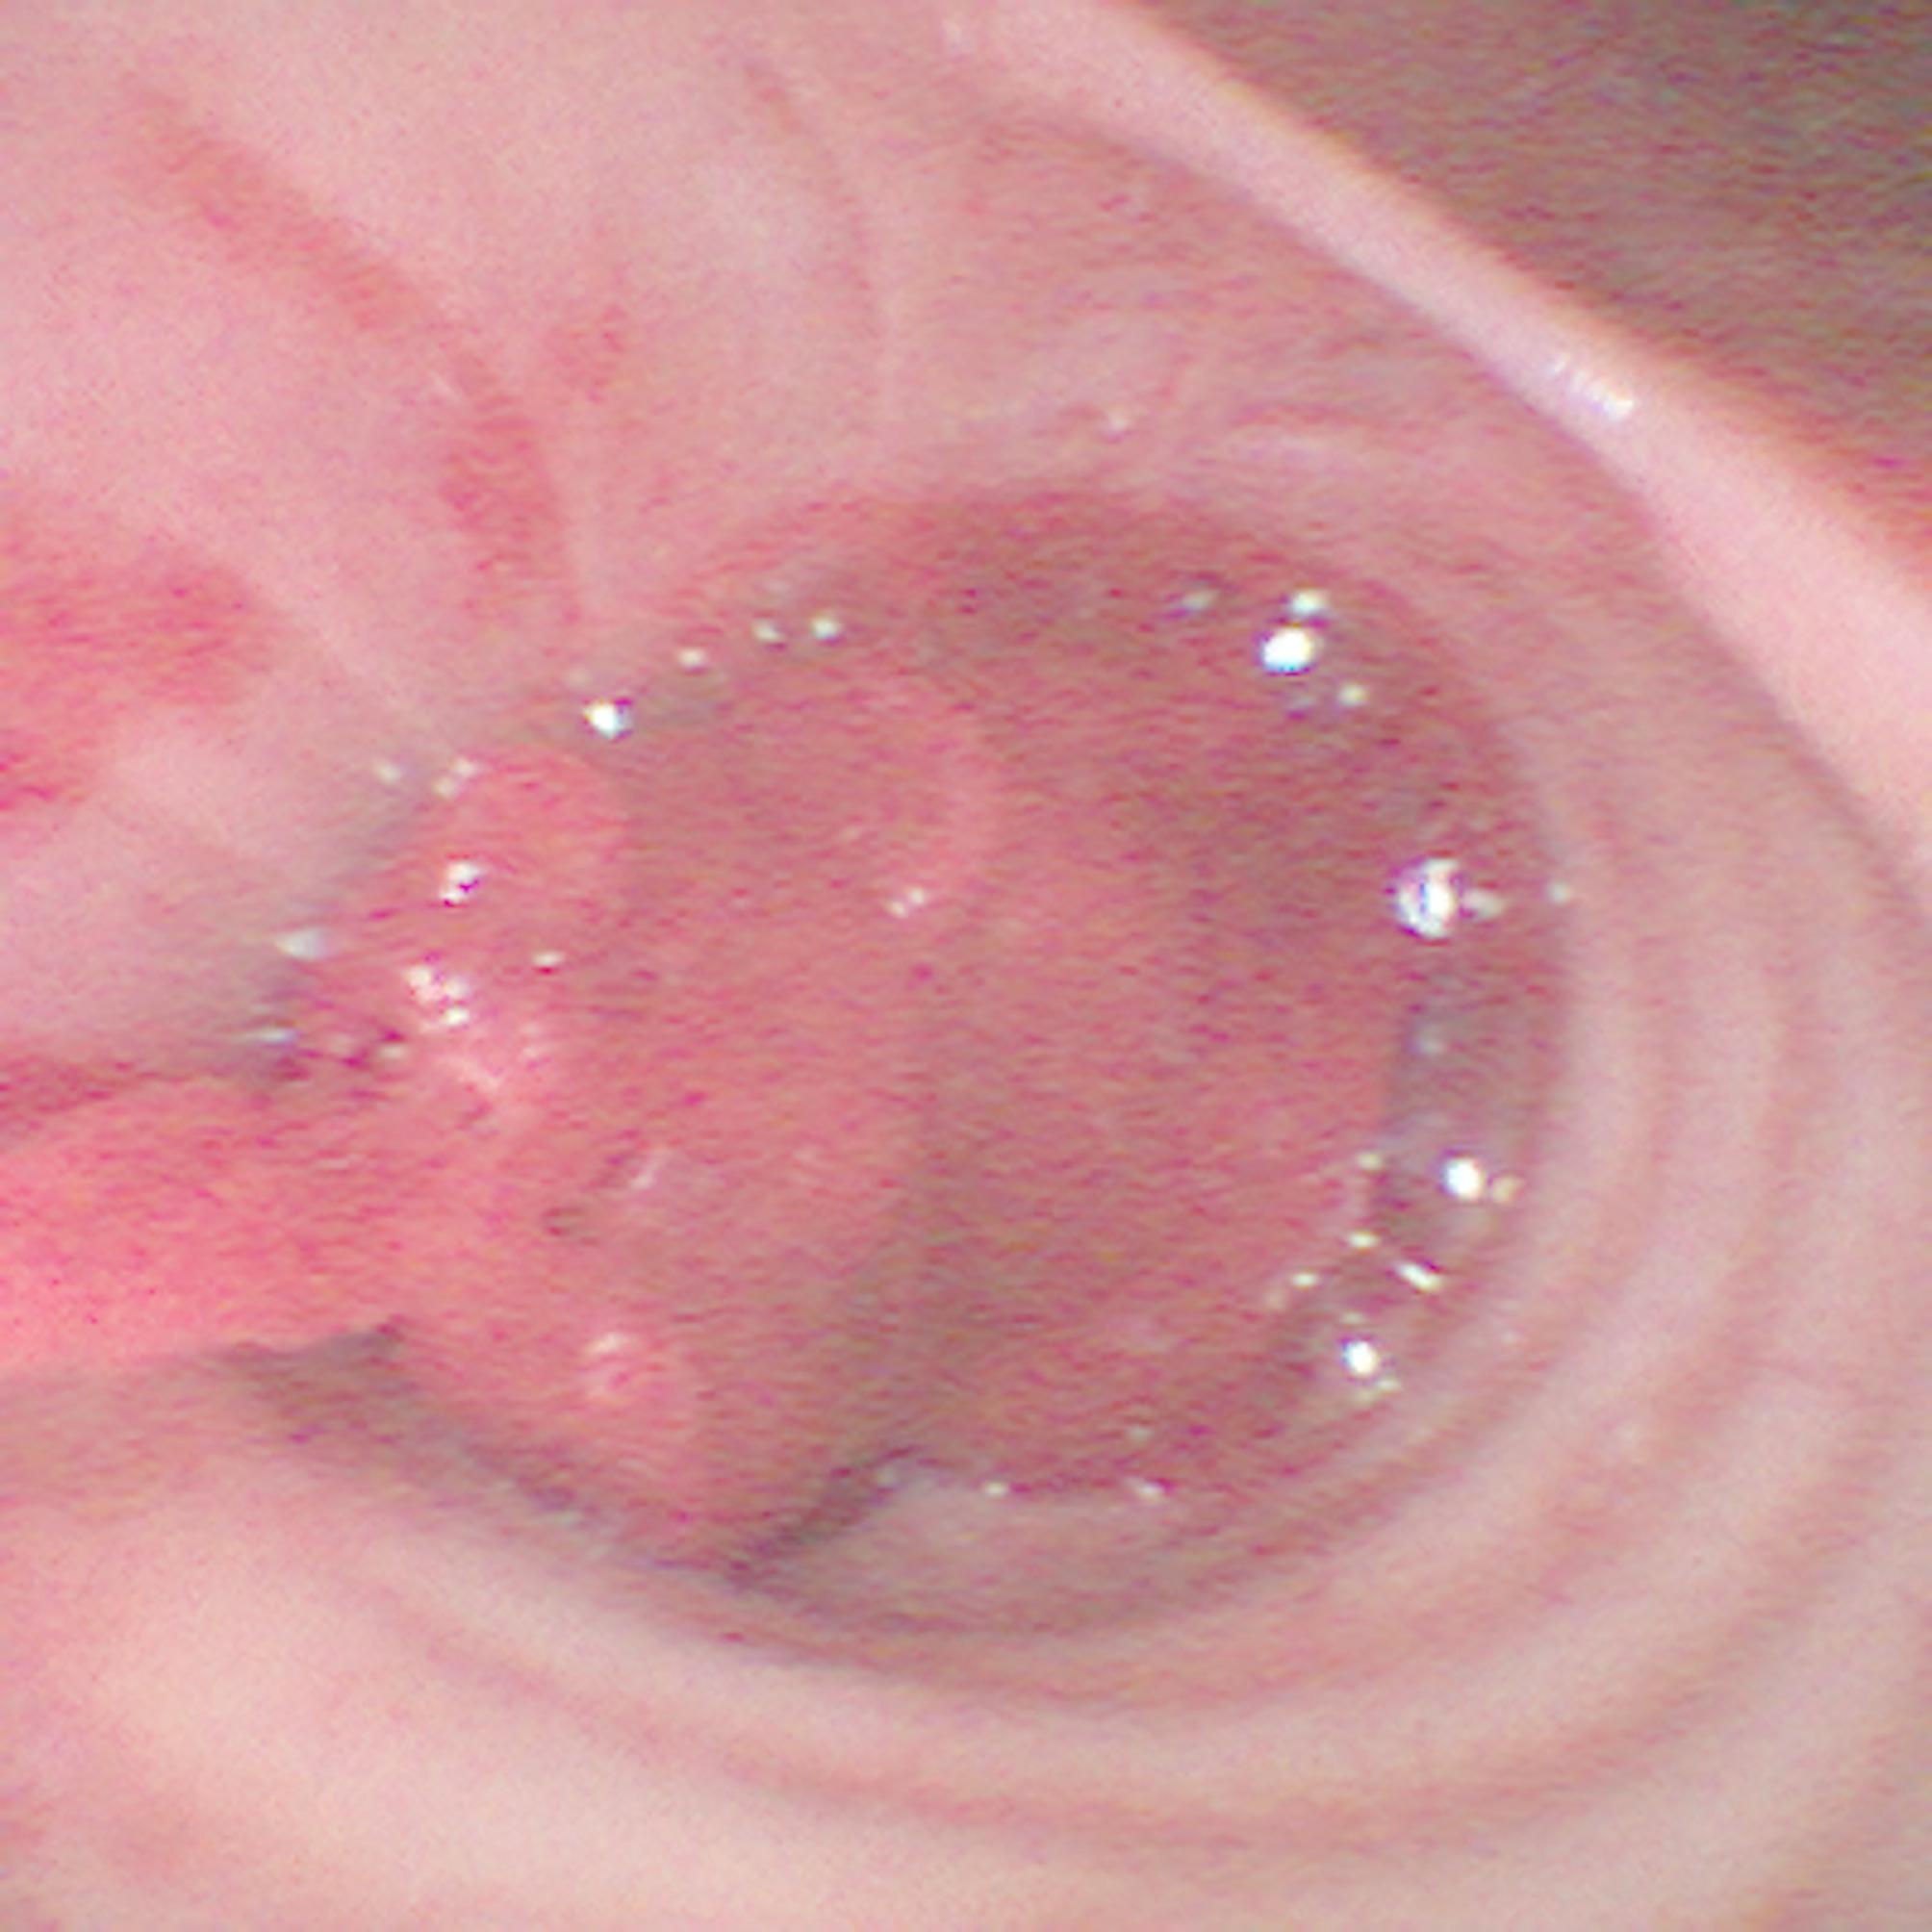

经皮扩张性气管切开术是一种成熟的技术,用于保护危重病人的气道。最常见的并发症之一是切口周围出血或解剖上邻近的大血管损伤后出血。我们报告一个病例,其中血小板减少的病人经历了危及生命的出血过程中,在分节支气管9和10,显然是由一个未识别的导丝诱导粘膜病变引起的。需要立即进行广泛的支气管镜检查和止血干预以确保氧合。为了更好地说明这种并发症,随后使用3D打印机创建了患者支气管系统的患者特异性(1:1)三维模型。总之,3d打印可以帮助可视化重症监护干预期间不常见的并发症。建议将导丝推进至气管隆突处于支气管镜控制下。字数:135。

Percutaneous dilatational tracheostomy is an established technique for securing the airway in critically ill patients. One of the most common complications is bleeding around the incision or after injury to major vessels in anatomic proximity.We report a case in which a thrombocytopenic patient experienced life-threatening bleeding during the procedure at the bifurcation between segmental bronchus 9 and 10, apparently caused by an unrecognized guide wire-induced mucosal lesion. Immediate extensive bronchoscopy and hemostatic interventions were required to ensure oxygenation. To better illustrate this complication, a patient-specific (1:1) three-dimensional model of the patient's bronchial system was subsequently created using a 3D printer. In conclusion, 3d printing can help to visualize uncommon complications during intensive care interventions. It is recommended to advance the guide wire the guide wire only until the tracheal carina under bronchoscopic control.Word count: 135.